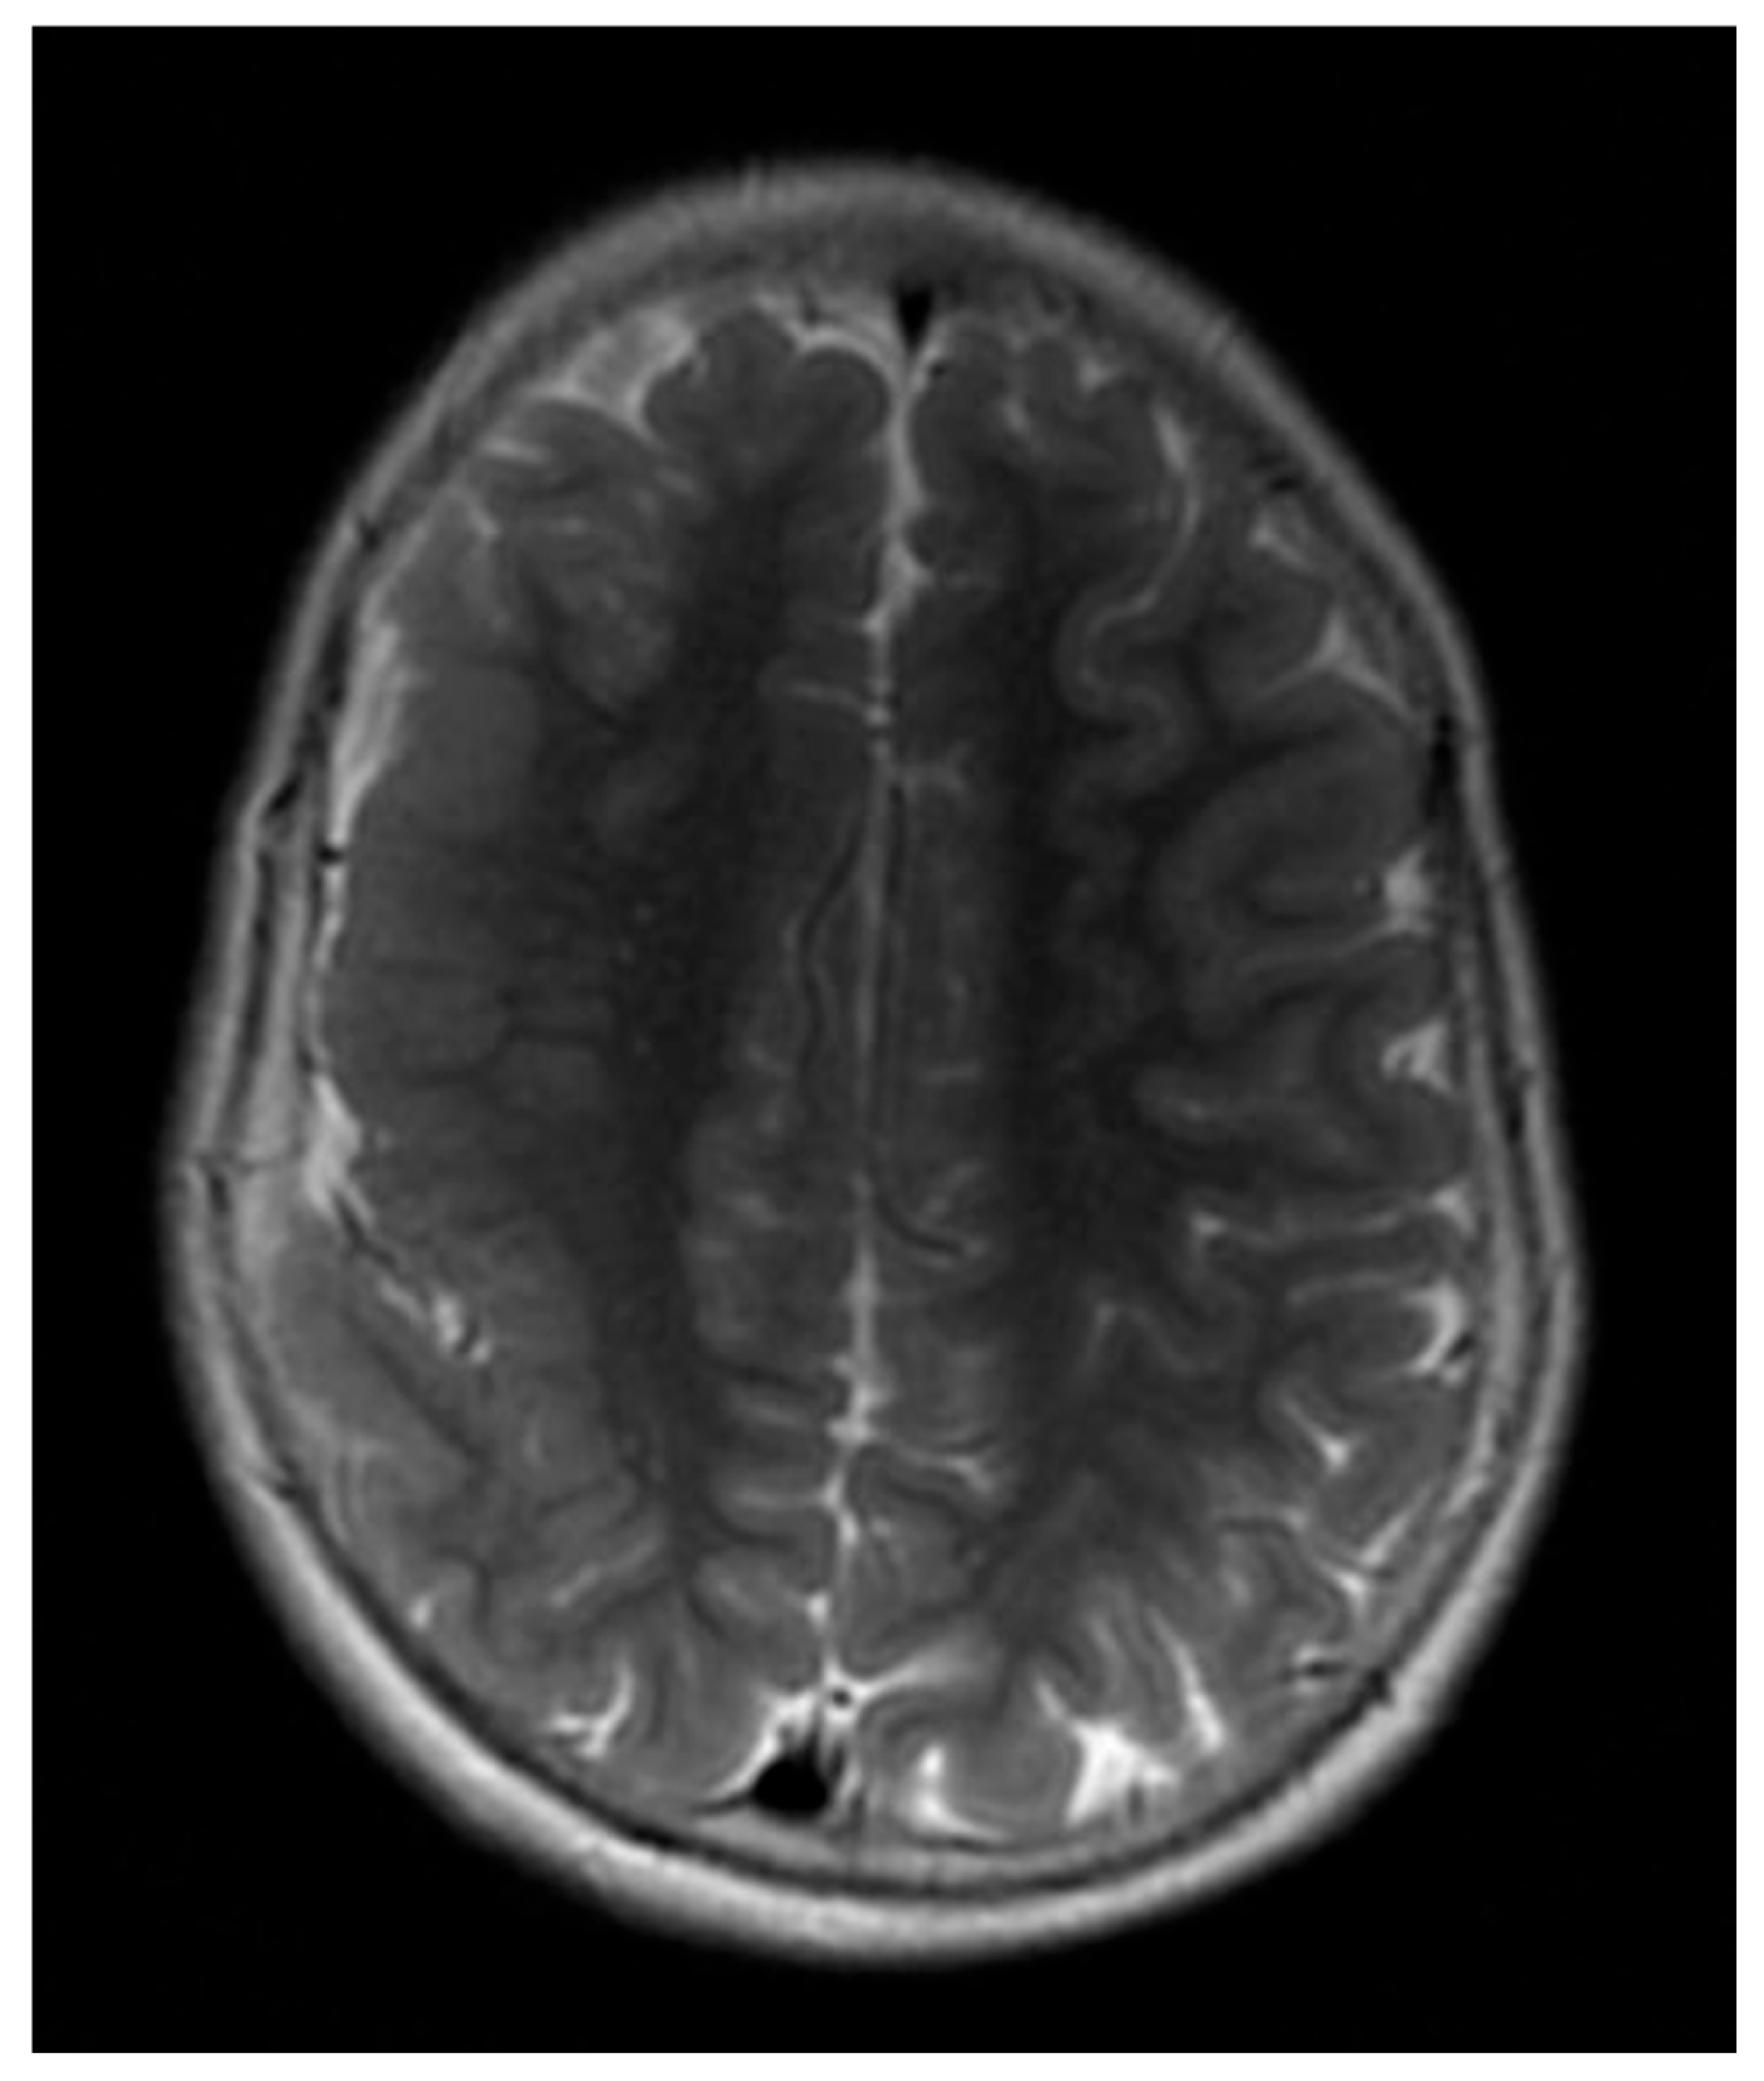

| 13 | Spike–wave and polyspike–wave (R); hypsarrhythmia | Diffuse polymicrogyria, thickened and dysplastic right fronto-parietal cortex; hypoplasia of the corpus callosum (Figure 7) | Not performed |

3.4. Neuroimaging